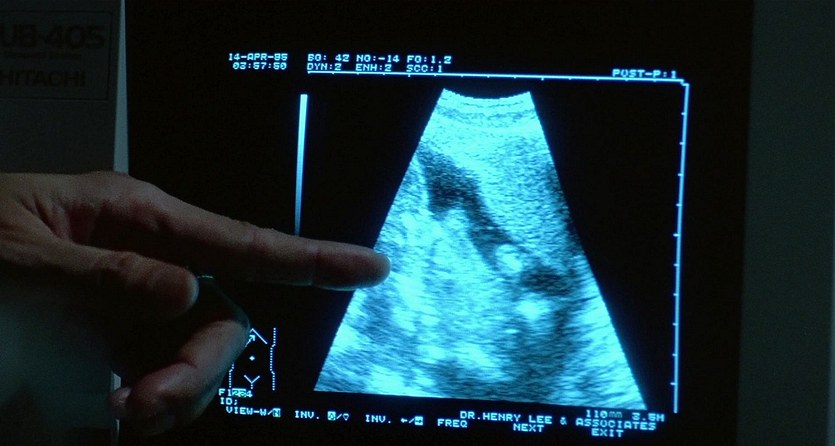

Great Adventurers (1995)

Name: The.Adventurers.1995_08860

Source: Blu-ray 1080p